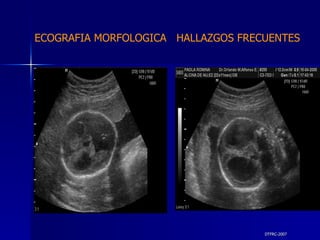

DTFRC-2007 ECOGRAFIA MORFOLOGICA  HALLAZGOS FRECUENTES   SISTEMA NERVIOSO CENTRAL TOTAL  8  26 % 1 HIDROCEFALIA 2 VENTRICULO MEGALIA 4 QUISTE DE PLEXO COROIDEO 1 ANENCEFALIA

DTFRC-2007 ECOGRAFIA MORFOLOGICA  HALLAZGOS FRECUENTES   GENITOURINARIA DISPLASIA RENAL MULTIQUISTICA  3 HIDRONEFROSIS  2 QUISTE DE OVARIO FETAL  1 SISTEMA DIGESTIVO DILATACION INTESTINAL  2  SISTEMA ESQUELETICO   PIE BOT  2  20 % 6 % 6 %